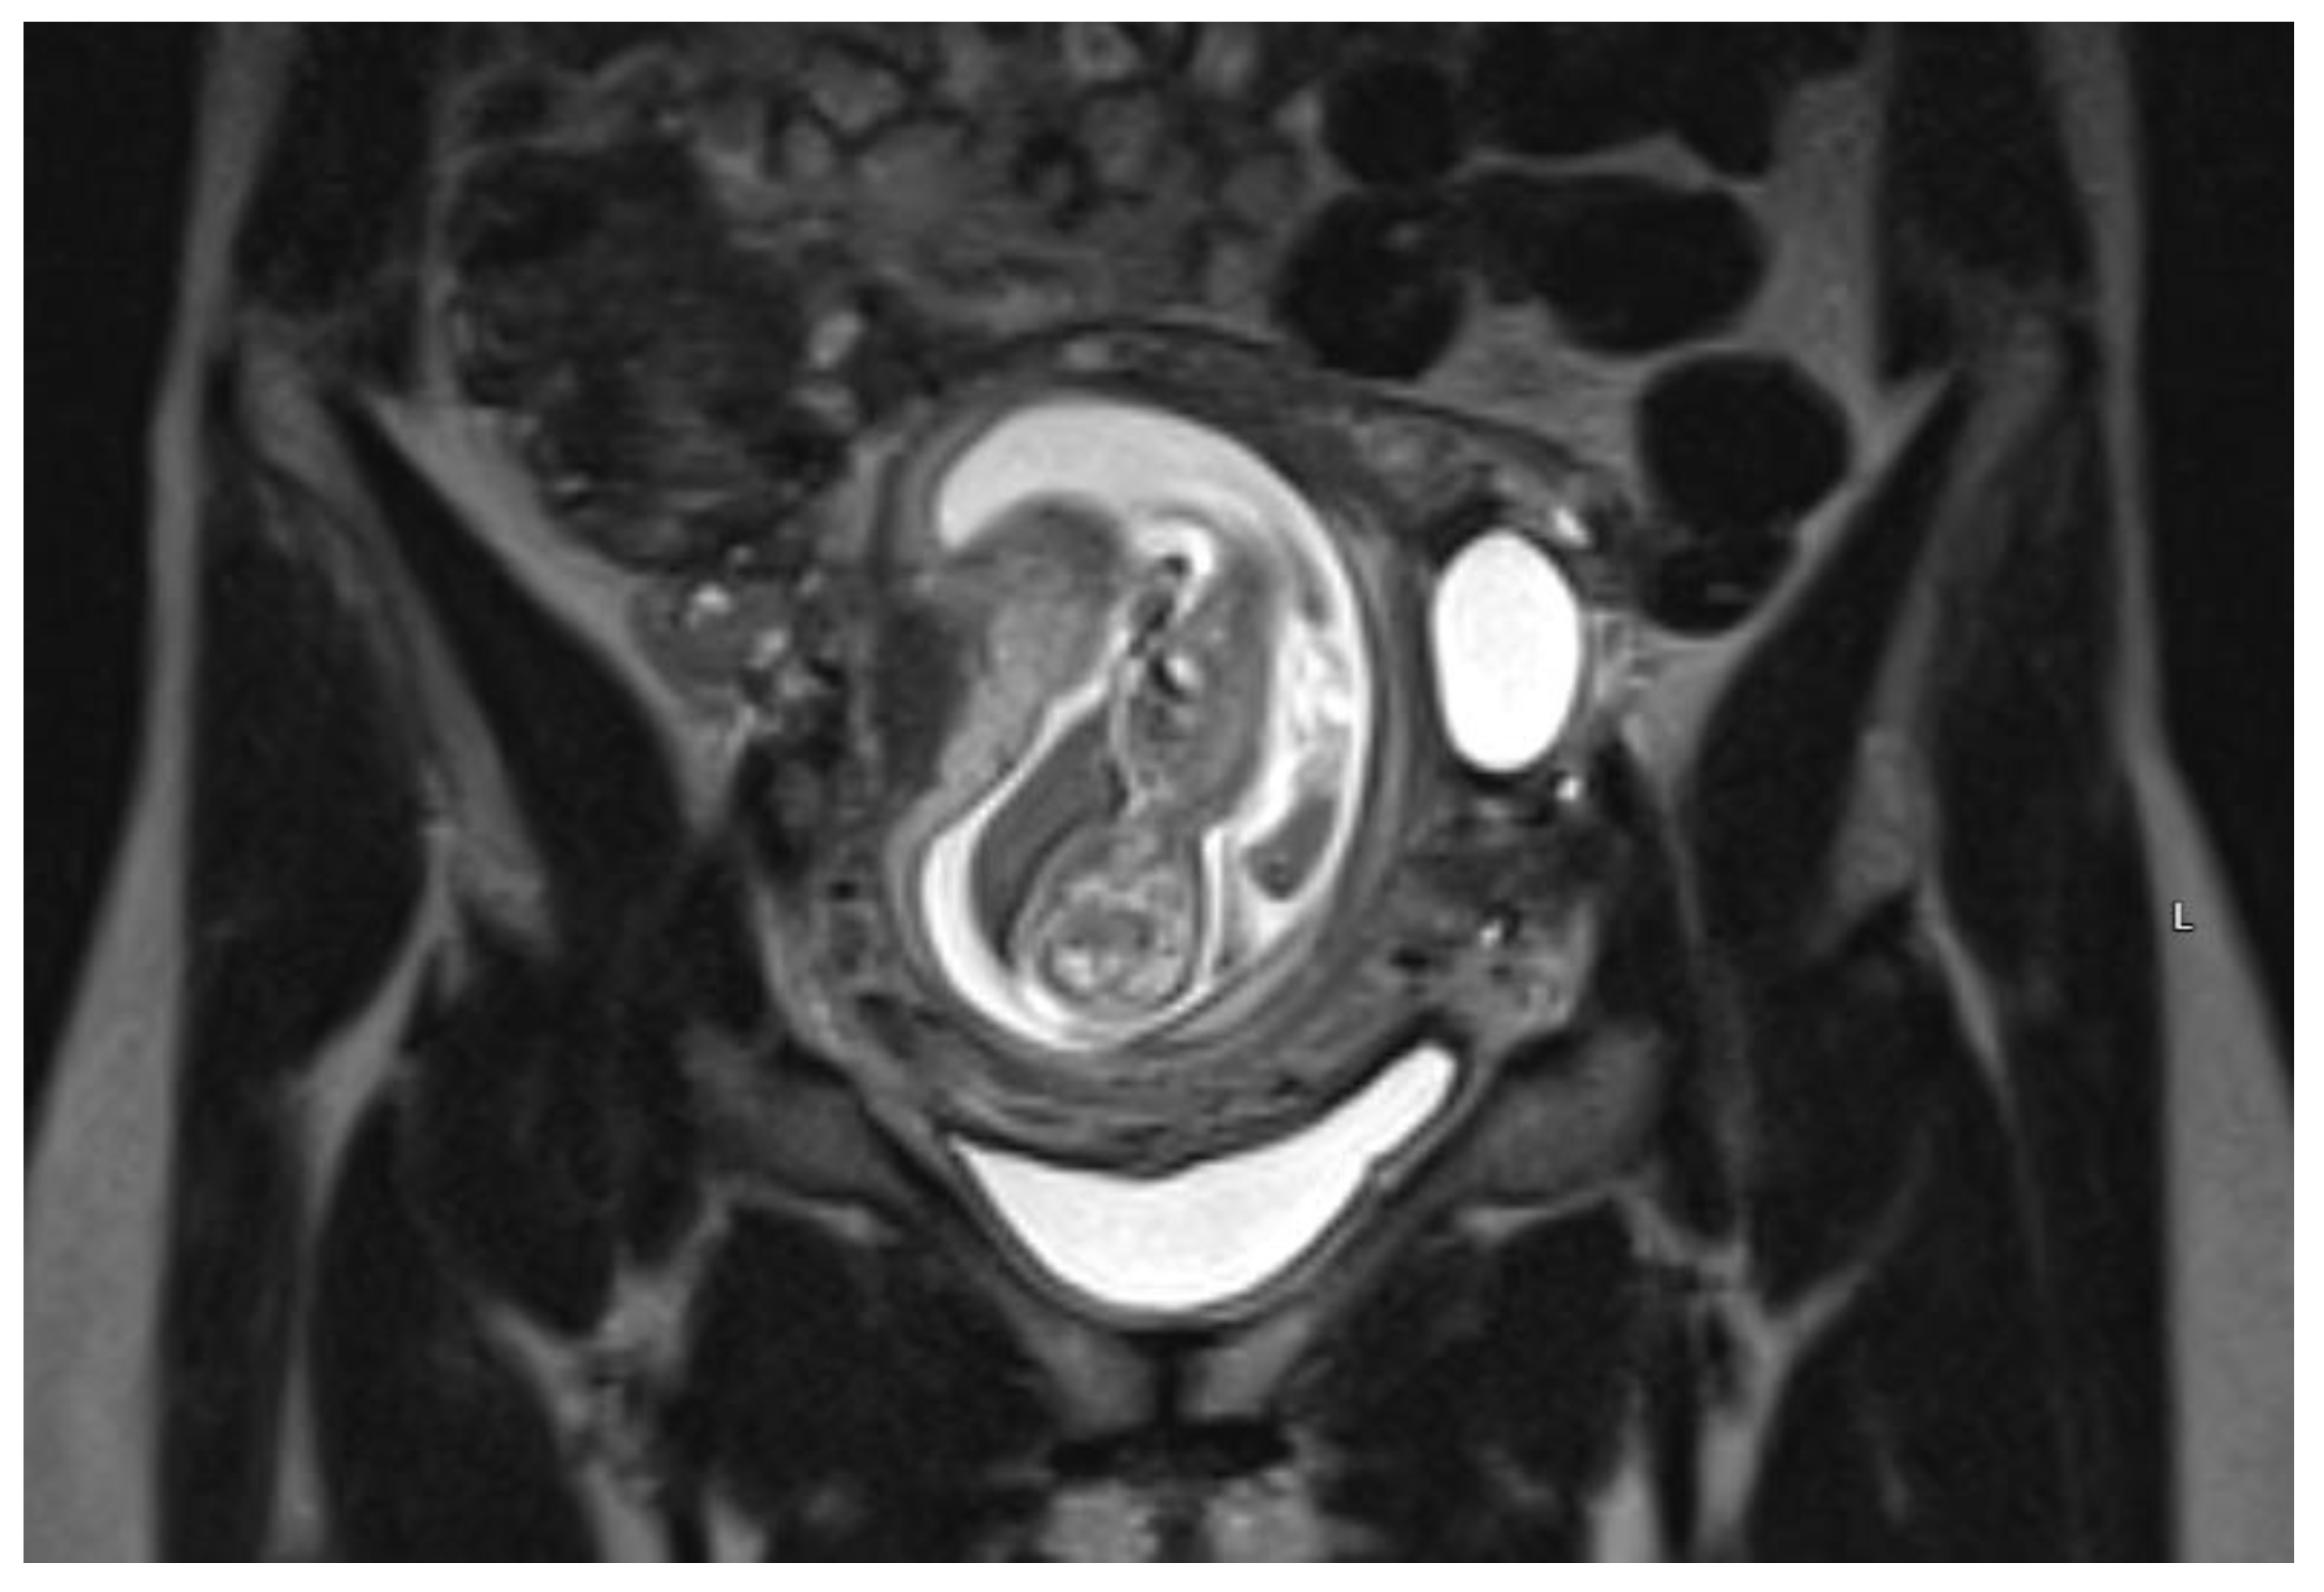

On admission, the patient’s vitals were stable. The patient reported episodic abdominal pain on the left side. Transabdominal ultrasound imaging revealed a hypoechogenic 3.05 × 3.08 cm size mass in the left cornu of the uterus, filled with fluid (without viable embryo), which, by evaluation of the blood flow, could have been related to the uterus. Figure 1.

Figure 1. Left cornu of the uterus visualized by transabdominal ultrasonography on the 13w + 3d.